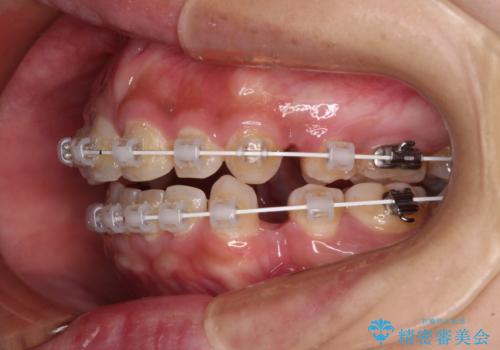

- 矯正装置

- 審美装置

- 治療期間

- 1年11ヶ月

通常は上下左右の第一小臼歯4本を抜歯することになりますが、右側臼歯部の咬合が上顎前突気味であったため、下顎右側のみ第二小臼歯を抜歯し、ワイヤー装置にて矯正治療を行うこととしました。